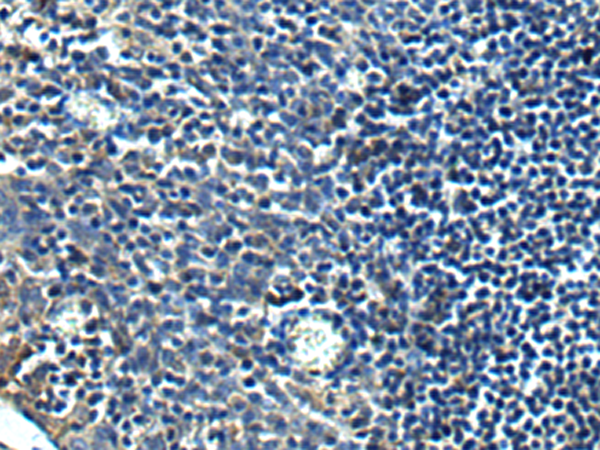

IHC positive control: |

Human tonsil |